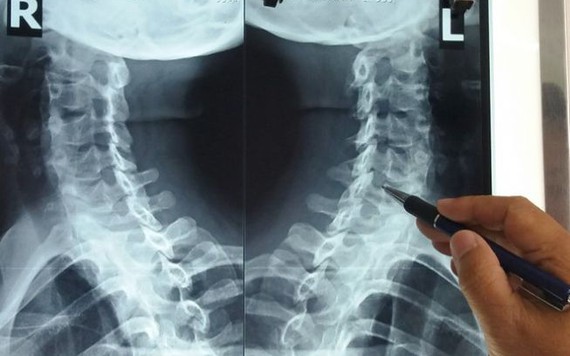

Dân văn phòng đừng chủ quan khi thoái hóa đốt sống cổ

Mỏi cổ gáy, vai và đau nửa đầu, hạn chế vận động mỗi khi xoay trở khớp cổ là những triệu chứng của thoái hóa đốt sống cổ - bệnh đang âm thầm tấn công giới văn phòng.